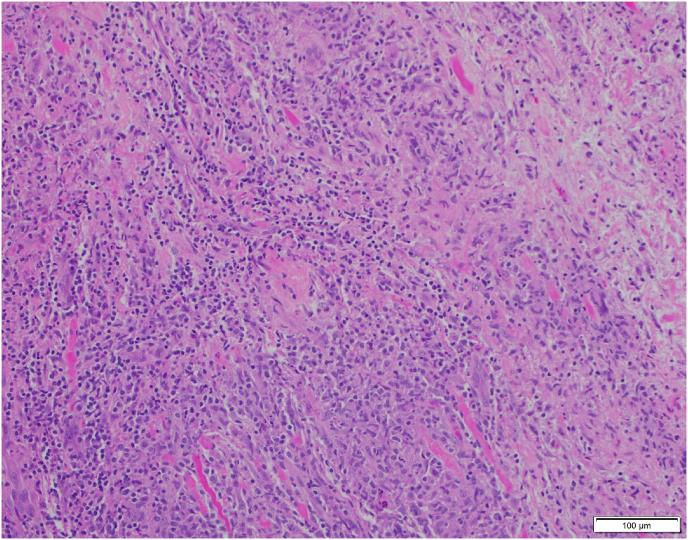

An 8-year-old male with a past medical history of chronic constipation who presented to the ophthalmologist in July 2017 with a 7-month history double vision, left upper lid ptosis, left abducens nerve palsy, and an abnormal thyroid test. The patient's family history was negative for any autoimmune disease including, juvenile idiopathic arthritis, rheumatoid arthritis, thyroid disease, type 1 diabetes mellitus or inflammatory bowel disease. Diagnosis of orbital pseudotumor of the left eye was made based on CT scan findings and he was then treated with a one-week course of oral prednisone. After resolution of his initial symptoms, he presented a month later with swelling in his left eye and was treated with a 6-month steroid taper with resolution of symptoms. In June 2018, the patient presented with swelling in his right eye and was treated with prednisone plus steroid sparing agents. Extraocular muscle biopsy was negative for IgG4 related disease, fungal infection, or malignant lymphoma and workup for sarcoidosis and granulomatosis with polyangiitis was unremarkable. In September 2018, the patient presented with bloody stools, diagnosed and treated for a perirectal abscess. Subsequent colonoscopy performed in January 2019 confirmed Crohn's disease. He is currently undergoing treatment with adalimumab and is in remission in terms of orbital pseudotumor.